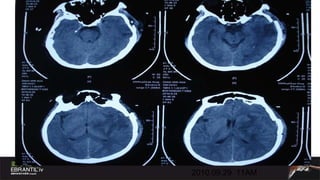

2010.09.29  11AM

Case Male,47ys 2010.09.17 9:17PM Sudden onset of headache and hemiparalysis Muscle strength 0 degree, GCS11 . BP180/120mmHg